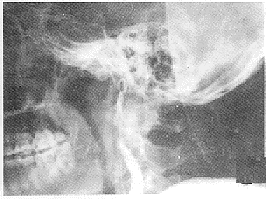

外傷性頸內動脈海綿竇瘺CT圖顱底骨折可造成頸內動脈海綿竇段或其分支損傷,或火器傷、銳器傷直接傷及動脈,或外傷時竇內段頸內動脈壁受到劇烈動盪血流的衝出而破裂,上述諸因素也可造成動脈壁的點狀出血或局限性損傷,以後因血壓的劇烈波動造成海綿竇段破裂。

外傷性頸內動脈海綿竇瘺CT圖1.局部症狀、體徵 是由於頸內動脈血流直接灌入海綿竇引起。